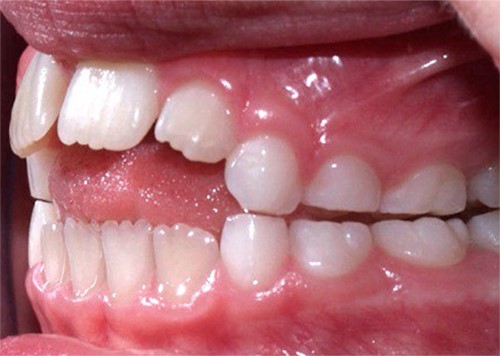

- Hábitos de succión prolongados: si tu hijo usa chupo o chupa dedo por un tiempo muy prolongado, sin tratamiento ni eliminación del hábito, esto puede causar problemas de mordida, entre ellos, apiñamiento dental. Si bien los hábitos de succión son un reflejo natural que proporciona sensación de seguridad y placer a tu hijo, es muy importante controlarlos, tal como los mencionamos en nuestros artículos, ¿Es malo que mi hijo chupe dedo? y ¿Es malo que mi bebé use chupete? , que pueden causar problemas de mordida como se muestran a continuación:

*Problema de mordida causado por chupar dedo, tomada de https://www.vela-lasagabaster.com/2018/03/22/malos-habitos-dentales-infantiles/